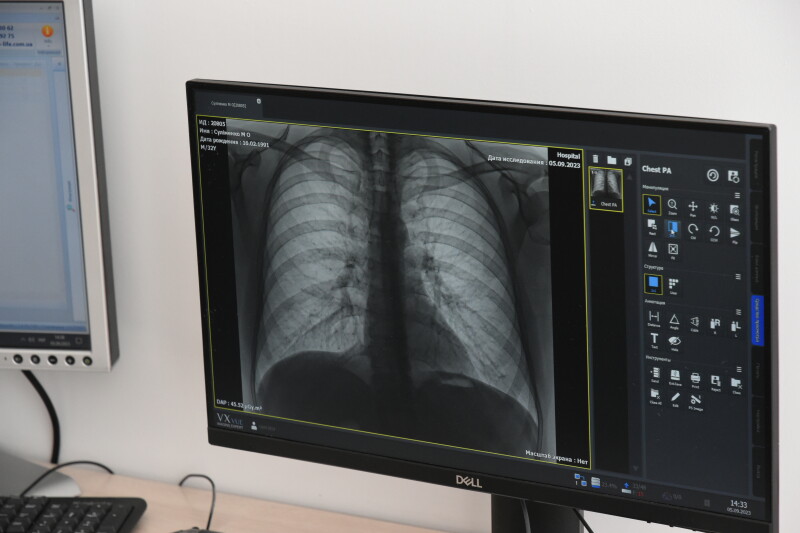

У рентгенологічному кабінеті провели ремонт, закупили меблі та сучасний цифровий рентгенологічний апарат “EcoView9 Plus” на 2 робочих місця. Відкрили другий кабінет ультразвукової діагностики, що дало змогу зменшити черги пацієнтів на проведення УЗД-обстеження внутрішніх органів.